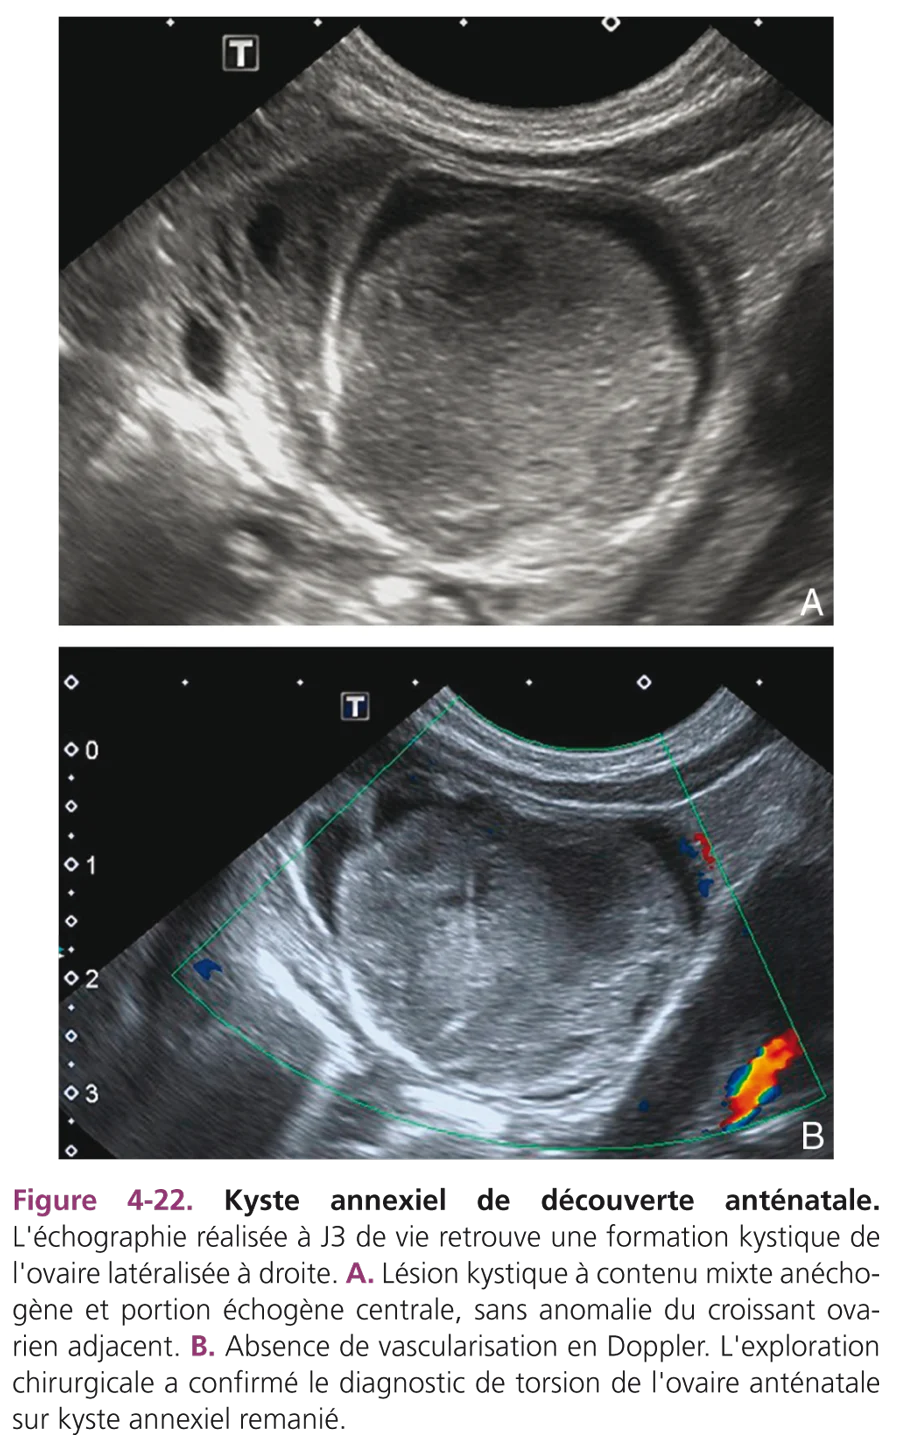

Chez un nouveau-né de sexe féminin, une masse liquidienne est un kyste de l’ovaire jusqu’à preuve du contraire. L’échographie est pratiquée pour confirmer un diagnostic anténatal ou pour étudier une masse abdominopelvienne palpée, ces kystes pouvant être très volumineux. Cliniquement, les kystes ovariens sont souvent latéralisés et mobiles, de topographie abdominopelvienne ou parfois abdominale, controlatérale à la situation d’origine. Il s’agit de kystes folliculaires simples, liquidiens, transsonores, à parois fines, de taille variable. Si le kyste est supérieur à 4 cm, le risque de torsion incite à pratiquer une ponction en période anténatale ou à la naissance (fig. 4-21).

En dehors de la torsion, l’évolution est spontanément favorable avec régression du kyste en moins de 6 mois. La récidive possible du kyste pendant environ 1 mois sous l’effet de la stimulation hormonale maternelle justifie une surveillance échographique. Les kystes ovariens peuvent présenter d’emblée un aspect trompeur d’échostructure hétérogène avec des échos de répartition irrégulière ou déclives avec niveau liquide ou d’échostructure homogène, échogène donnant un aspect de masse solide (fig. 4-22A). Ces aspects sont liés à une hémorragie intrakystique spontanée, traumatique ou secondaire à une torsion du fait de l’étirement de la trompe adjacente. Le diagnostic de torsion est difficile au Doppler car l’altération du flux n’est pas toujours appréciée de façon fiable (fig. 4-22B). Ces kystes hémorragiques sont en général opérés, bien que la récupération de l’ovaire soit aléatoire.